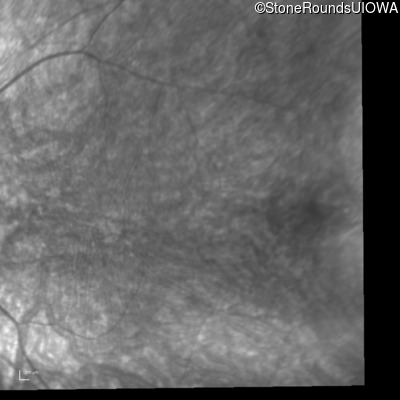

Infrared Fundus Photograph - Right - 20/100 -1 sc

Exemplar

Infrared Fundus Photograph - Left - 20/100 -2 sc